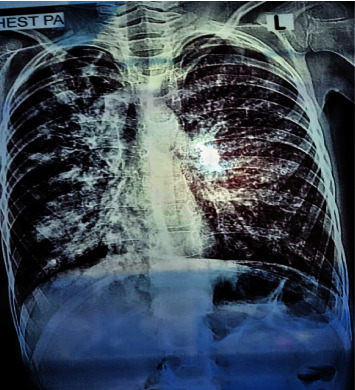

Cystic fibrosis (CF) is a genetic monogenic disorder inherited in an autosomal recessive manner, marked by persistent airway infections in the endobronchial region. This condition leads to the gradual development of bronchiectasis and, ultimately, respiratory failure, emerging as the primary cause of mortality in individuals diagnosed with CF. Diagnosis is done depending on the patient's symptoms and lung radiological findings like chest X-rays and CTs. In younger patients and children, diagnosis becomes difficult due to overlapping symptoms with other diseases such as CF which is a rare genetic disease in our population. Diagnosis of CF usually relies on characteristic symptoms, a family history of CF, and an abnormal sweat chloride test, but in children, low sweat production during testing leads to false negative results. In this case report, a suspected patient with ambiguous respiratory symptoms underwent a comprehensive investigation revealing elevated CRP levels, TLC, and characteristic pulmonary manifestations on chest X-ray, suggesting cystic fibrosis. Despite negative sweat chloride tests, the patient was analysed for potential candidate SNPs and was also tested for potential CFTR mutations to rule out CF, genetic analysis confirmed the diagnosis. Genetic testing plays a crucial role in diagnosing cystic fibrosis, even when traditional tests are inconclusive. Specific mutations like Δ508 deletion and rs213950 guide personalized treatment. Consanguinity and family history highlight genetic predisposition, while environmental factors may influence symptom onset. Further research is needed to understand these complexities and improve diagnostic and treatment approaches.